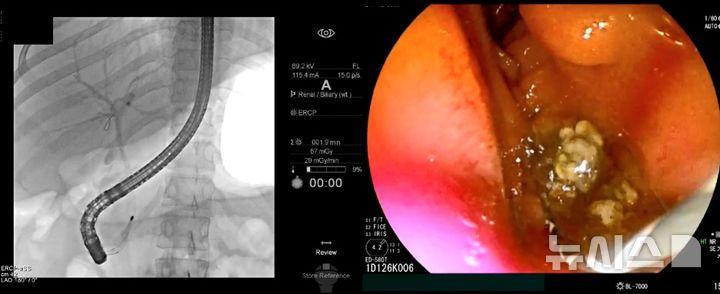

초음파내시경으로 담관결석이 관찰되면 내시경적 역행성 담췌관조영술(ERCP)을 통해 담관결석을 제거한다. ERCP는 담석의 정확한 위치를 확인하기 위한 특수내시경과 방사선을 이용한 시술이다. ERCP로 담관결석을 제거한 뒤에도 재발을 막기 위해 담낭담석을 제거하는 담낭절제술이 필요하다.